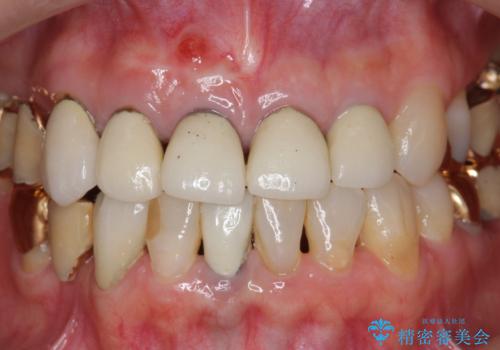

即切歯の抜歯を行う場合犬歯を含めたブリッジによる補綴計画を立てることが多いですが、今回は犬歯から大臼歯にかかる大きなブリッジが既に装着されていたため予算とご希望を相談し前歯のみの延長ブリッジ補綴で治療を行っていくこととしました。

- 54万円(仮歯・感染根管治療・ファイバーコア・ジルコニアクラウン×4) (税別)費用は治療当時の料金となります

歯列全体を治療の対象とする治療計画が予算や期間により難しい場合、状況に応じて最善の治療結果が出せるよう治療のゴールを相談しながら決定することが可能です。